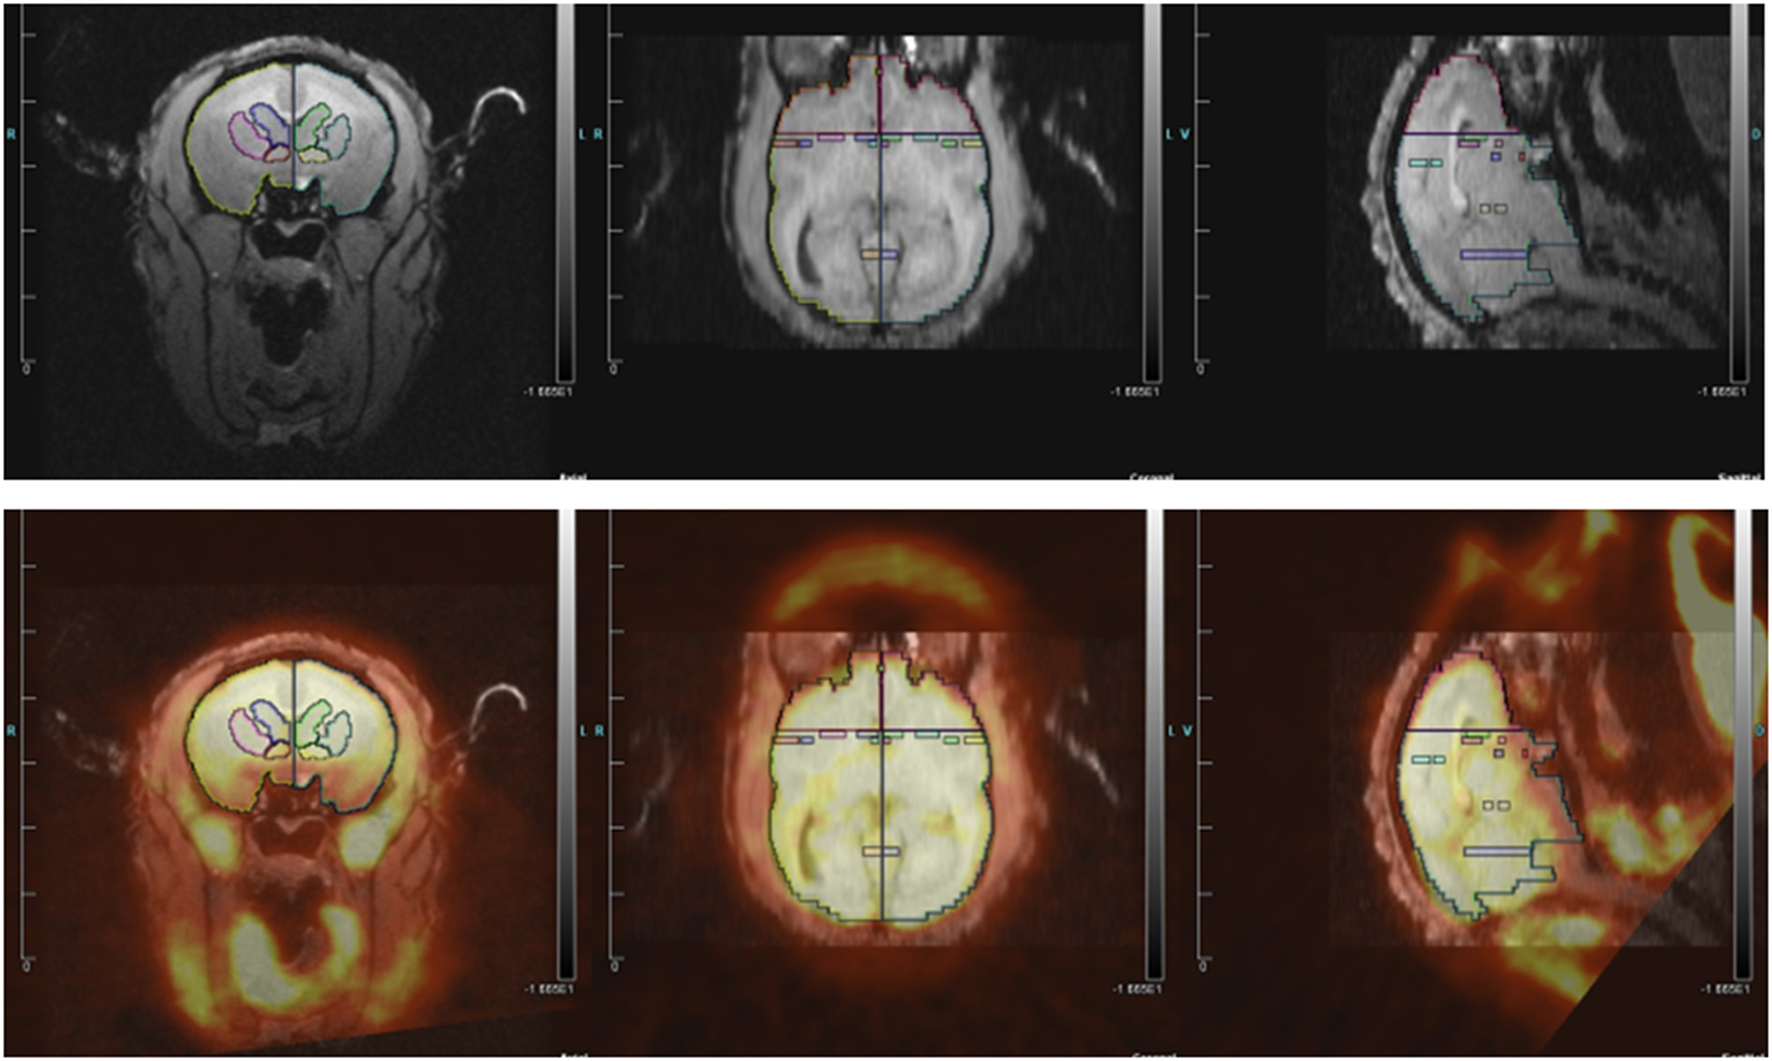

PET and MRI Coregistration, Quantification of FDG Uptake

We determined which regions of interest (ROIs) to quantify based on three groups of studies: rodent studies of aggression (lateral septum, medial amygdala, posterior cingulate cortex, and anterior hypothalamus), the Rilling rhesus monkey study of consortship (superior temporal cortex, insular cortex), and human studies of social pain and jealousy (anterior cingulate cortex, nucleus accumbens, ventral pallidum, caudate, and putamen) (Figure 2).

Figure 2. (Top) MRI image with regions of interest. (Bottom) MRI image co-registered with PET for titi monkey in jealousy condition.

ROI structures were individually drawn on each subject's MRI image, for both left and right hemispheres, using landmarks as a guide, in Siemen's Inveon Research Workplace software (IRW, Siemens Healthcare, USA). ROIs were drawn prior to co-registrations with the PET image, so they were drawn blind with regard to PET image/FDG uptake and to experimental condition. The same ROIs were used for both the jealousy and control conditions. Static PET images were reconstructed with a 3DRP reconstruction protocol. MRI images were co-registered with PET scan images using the automatic rigid registration algorithm in IRW and checked visually for registration accuracy. Mean activity for the PET images were determined in IRW by applying ROIs defined on the MRI images to the PET images. Data are presented in proportions of whole brain activity, which was calculated by dividing the mean activity in the ROI (in units of microcuries per cubic centimeter) by mean activity of whole brain ROI.